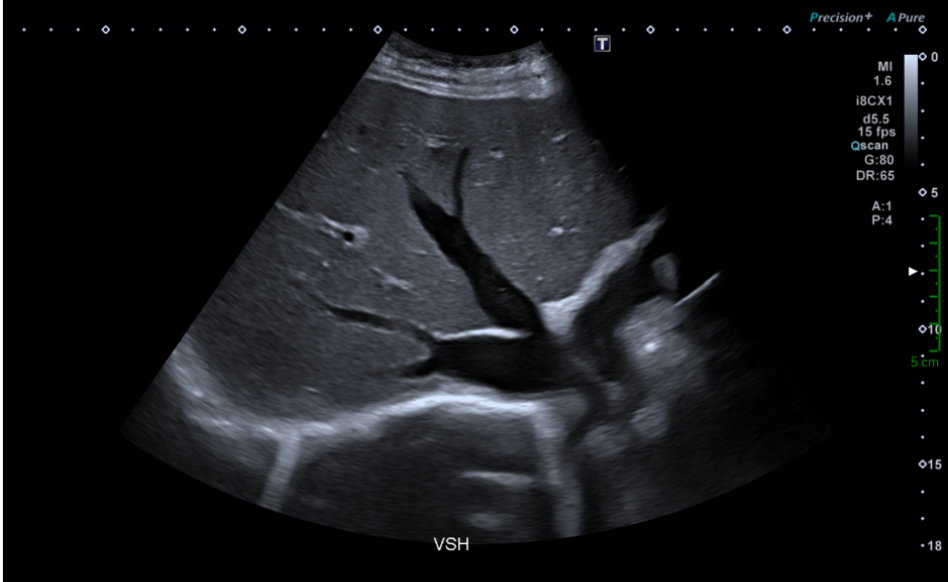

Une échographie abdominale est réalisée chez un patient se présentant pour un bilan de cholestase et un ictère cutanéo-muqueux. Il n’a pas d’antécédent hépatique connu et ne présente pas de douleur abdominale.

L’échographiste détecte un foie homogène, sans lésion focale, sans signe de dysmorphie, aux contours réguliers, une rate homogène de taille normale.

Les voies biliaires ne sont pas dilatées.

Par contre le foie est augmenté de taille de façon harmonieuse.

De plus, le flux du tronc porte attire son attention.